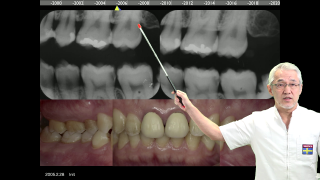

勤務医時代の私は、病態がわからないとすぐにX線写真を撮影していた。

しかしながら現像されてきても「やっぱりわからない」事がほとんどだった。

歯髄炎は「凄く痛いもの」患者さんは痛さを「ずきずきする」と表現するもの、と勘違いしていた。

そうったことすべてを覆したイエテボリ診断学教室で学んだ「診断の技術」をお届けしたいと思う。